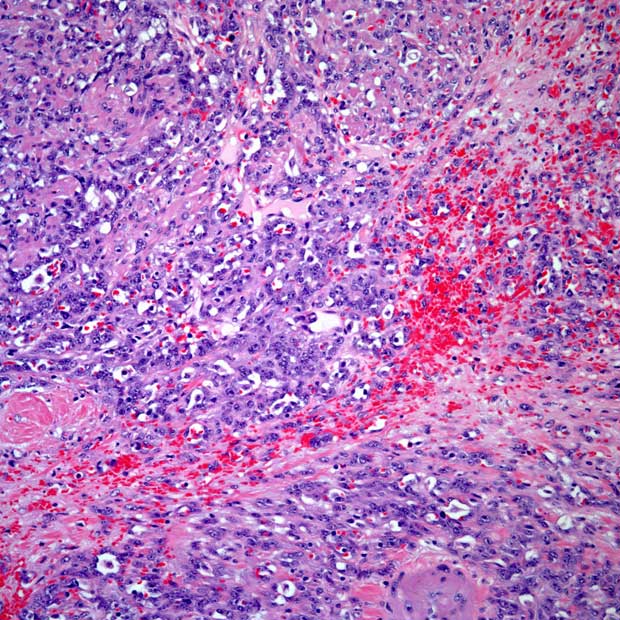

During Morning Rounds, Petros Grivas, MD, and his treating team debate the diagnosis of a patient with urothelial carcinoma as it has an unusual presentation.